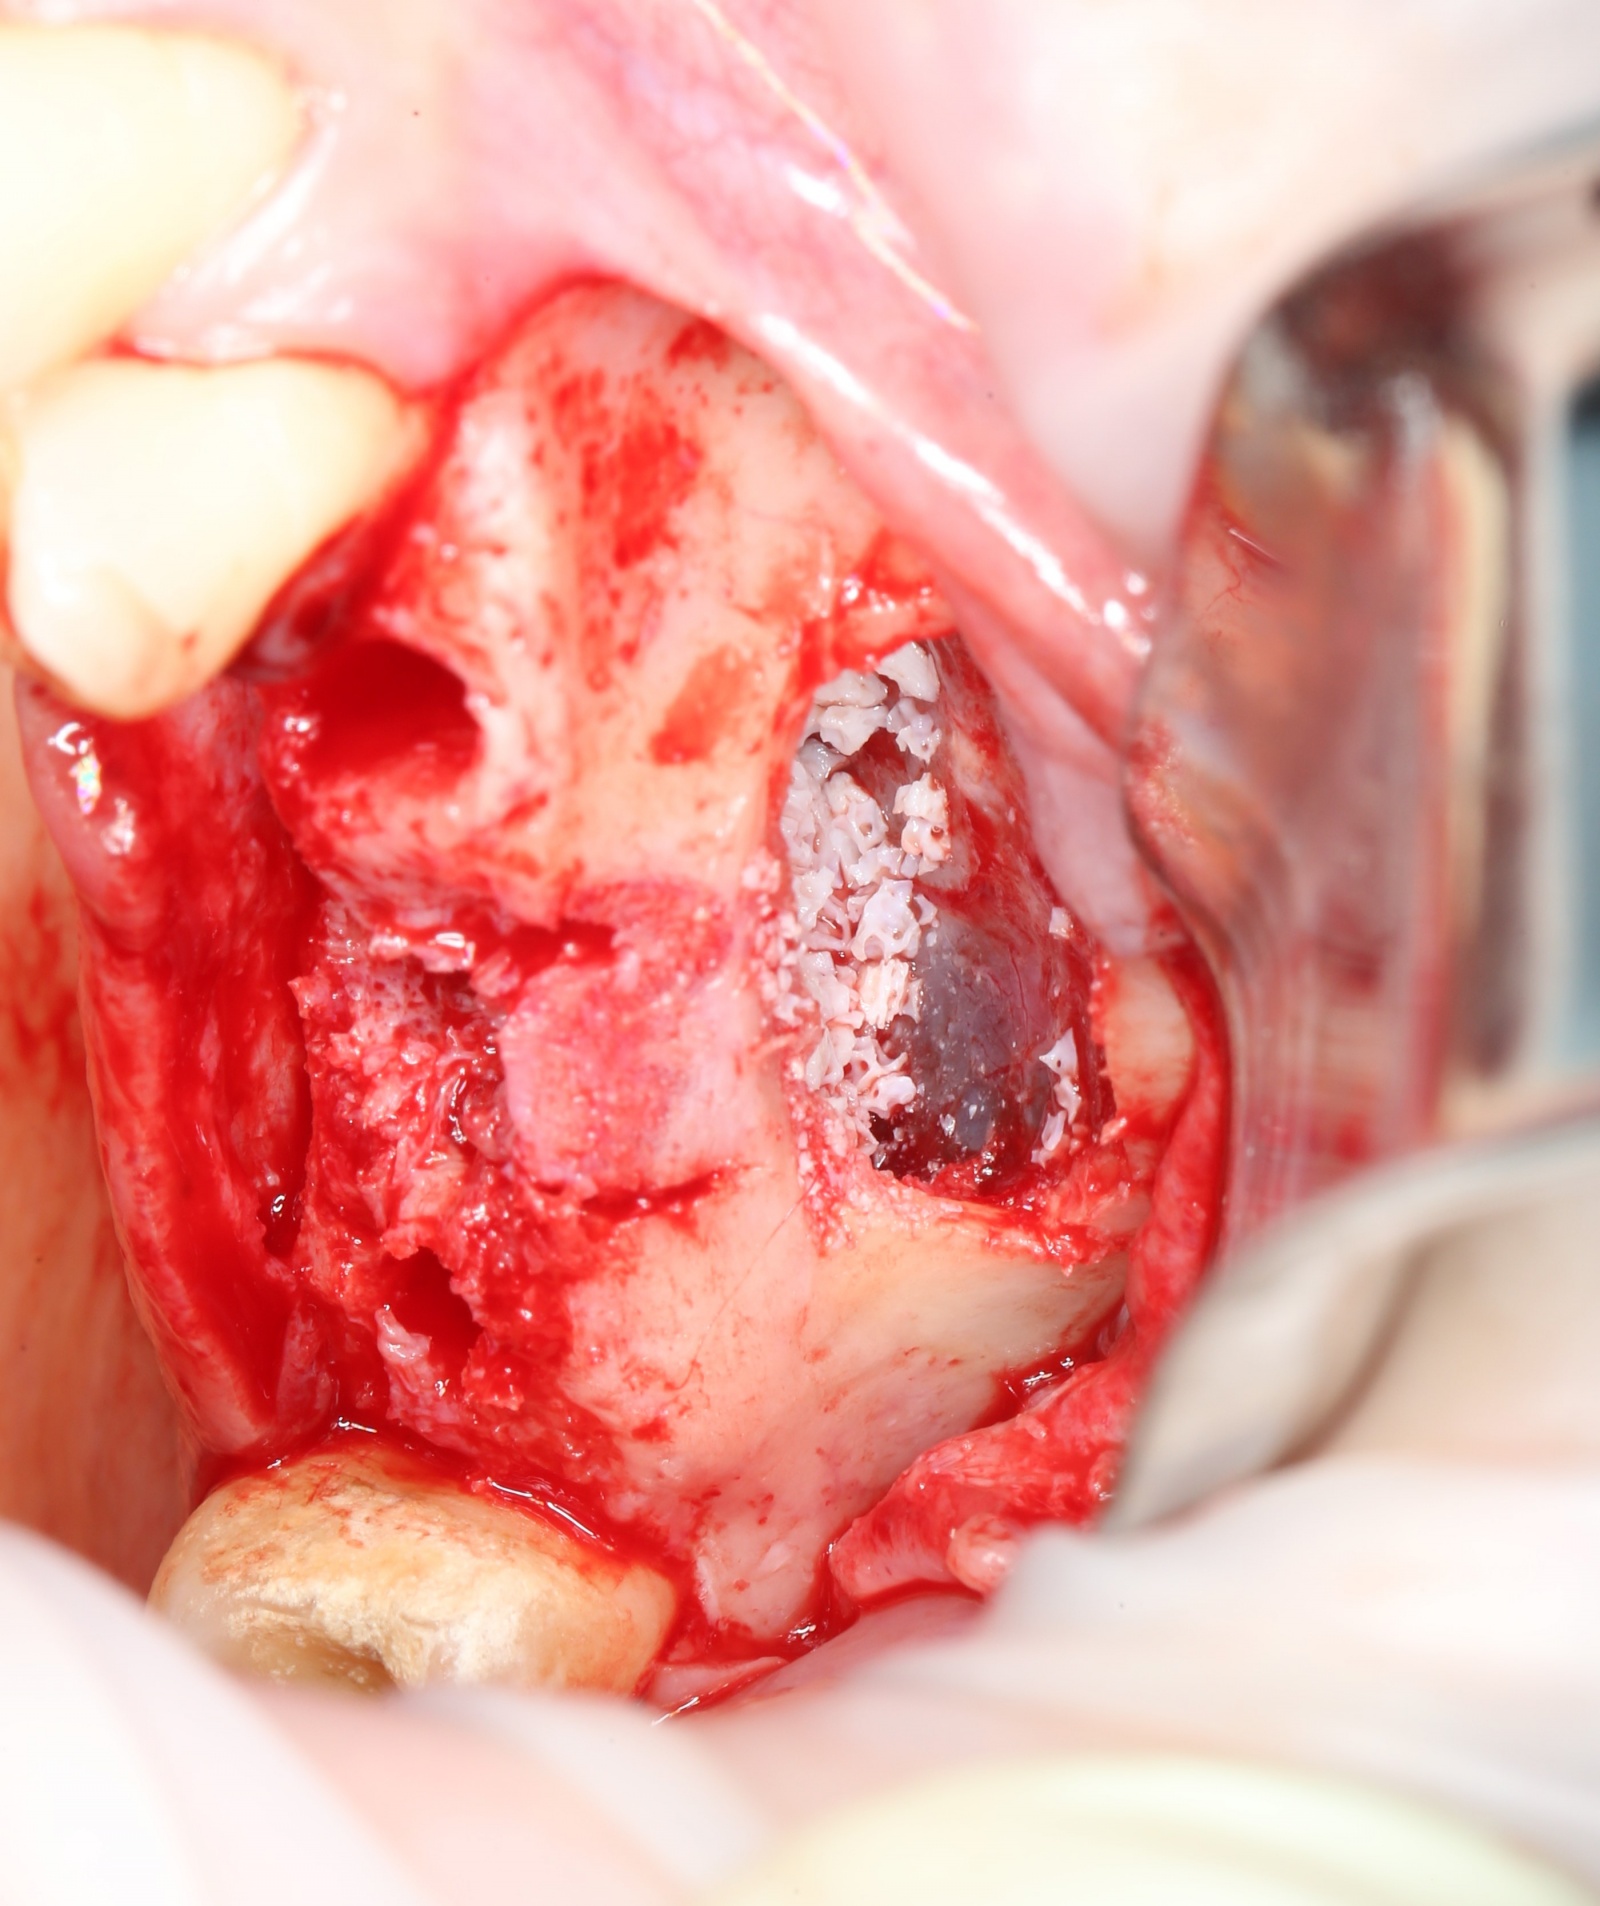

Производится внесение костного материала.

Он выпускается как в стеклянных баночках,

так и в специальных шприцах, с помощью которых его удобнее вносить.

Так это выглядит в полости рта:

Костный материал распределяется порционно:

Со стороны сформированных лунок можно проконтролировать его распределение:

Четко видно, что костная стружка уложена именно там, где будут располагаться имплантаты.

Далее укладывается дополнительная порция костного материала, а «окно» закрывается «крышкой», которая была вырезана ультразвуковым наконечником: